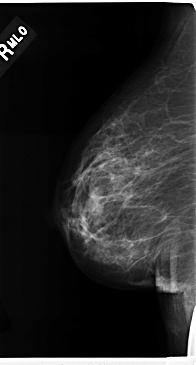

C_0206_1.RIGHT_MLO

RIGHT_CC LINES 4712 PIXELS_PER_LINE 2296 BITS_PER_PIXEL 12 RESOLUTION 50 NON_OVERLAY

RIGHT_MLO LINES 4736 PIXELS_PER_LINE 2536 BITS_PER_PIXEL 12 RESOLUTION 50 NON_OVERLAY